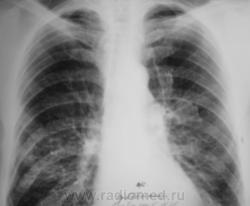

Отдельные снимки этого пациента выставлялись на сайте, но мы никогда не имели полного "набора", так как рентгенологические исследования проводились в трех ЛПУ - у нас и в двух ЛПУ областного уровня (спец. ЛПУ), где пациент получал специфическое лечение. Сегодня, мы имеем полный набор снимков, и мне показалось целесообразным выставить, именно, динамику....

Пациент был взят на контроль в 2009 году, было произведено дообследование в виде томографии в стандартных срезах, был заподозрен очаговый туберкуулёз, который был подтвержден " в области" и пациент был взят на учет. Было назначено специфическое лечение.

Через некоторое время было произведено плановое контрольное обследование.